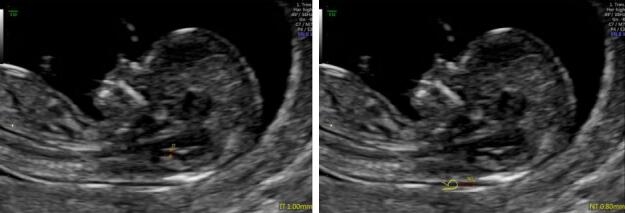

中孕期彩超胎儿颜面部及脊柱成像,把胎儿看的真真切切,明明白白,让您提前观察到宝宝的一举一动,一颦一笑,准妈妈们可以亲眼目睹胎儿在子宫内的相貌和动作,在感叹生命发生的同时,留下一段珍贵的影像,一段属于您和宝宝最早最珍贵的回忆。

生气了 哈哈-- 睁眼睛了

思考一下 光太亮了 好好睡一觉吧

做了个好梦 别惹我

胎儿脊柱成像 看我的脚丫子胖不胖····

挠一挠 唇裂

故三维、四维容积超声对诊断胎儿神经系统学,表面成像的胎儿畸形的筛查有更直观的感受,更明确的帮助诊断。